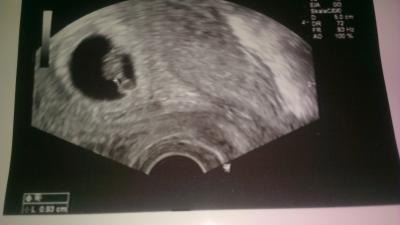

Hey :) Auch ich war heute morgen beim Arzt und es wurde gleich alles erledigt-war ca. 1,5 h dort...haben viele fragen gestellt und den mutterpass ausgestellt und auf dem Ultraschall habe ich heute die fruchthòhle, Dottersack und den 9mm großen Embryo inkl. Zartem herzchen gesehen < 3 nach meinen Berechnungen wäre ich heute bei 7+0/1. Sie meinte/laut Ultraschall bin ich 6+5. Herzlichen Glückwunsch auch an alle,die heute beim FA waren!bzw. Wünsche ich natürlich allen hier nur das beste :)!